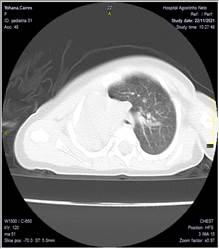

Se realizó una tomografía axial computarizada de tórax evidenciándose hipoplasia pulmonar fig. 1

Se realiza espiral tomográfico axial simple a 5 mm de tórax con reconstrucciones axiales milimétricas, sagitales y coronales en equipo multicorte observándose asimetría de ambos hemitórax, siendo mayor el derecho de aspecto compensador con desplazamiento de las estructuras del mediastino a la izquierda. Pulmón izquierdo pequeño. Presencia de disminución del calibre de los vasos pulmonares, así como el aparato bronquial.

Conclusión. Hipoplasia pulmonar izquierda

Fig. 1. Tomografía axial de tórax. A. corte axial. B. corte coronal. C. corte sagital

Tomografía de tórax: Opacidad homogénea en hemitórax izquierdo con desplazamiento de las estructuras del mediastino, reducción del volumen pulmonar derecho.